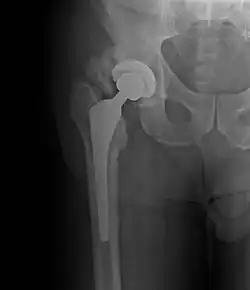

• Hip most common - typically after ORIF (52% any grade, 19% Grade III-IV) or THA (43% any grade, 9% Grade III-IV)

Hip surgery risk factors

Patient Clinical Surgical

History of HO T-type fracture Lateral/anterolateral approach

Male Fracture with dislocation Trochanteric or femoral osteotomy

Hypertrophic OA Multiple injuries Extended iliofemoral approach

Ankylosing spondylitis

Skeletal hyperostosis

Prior hip surgery